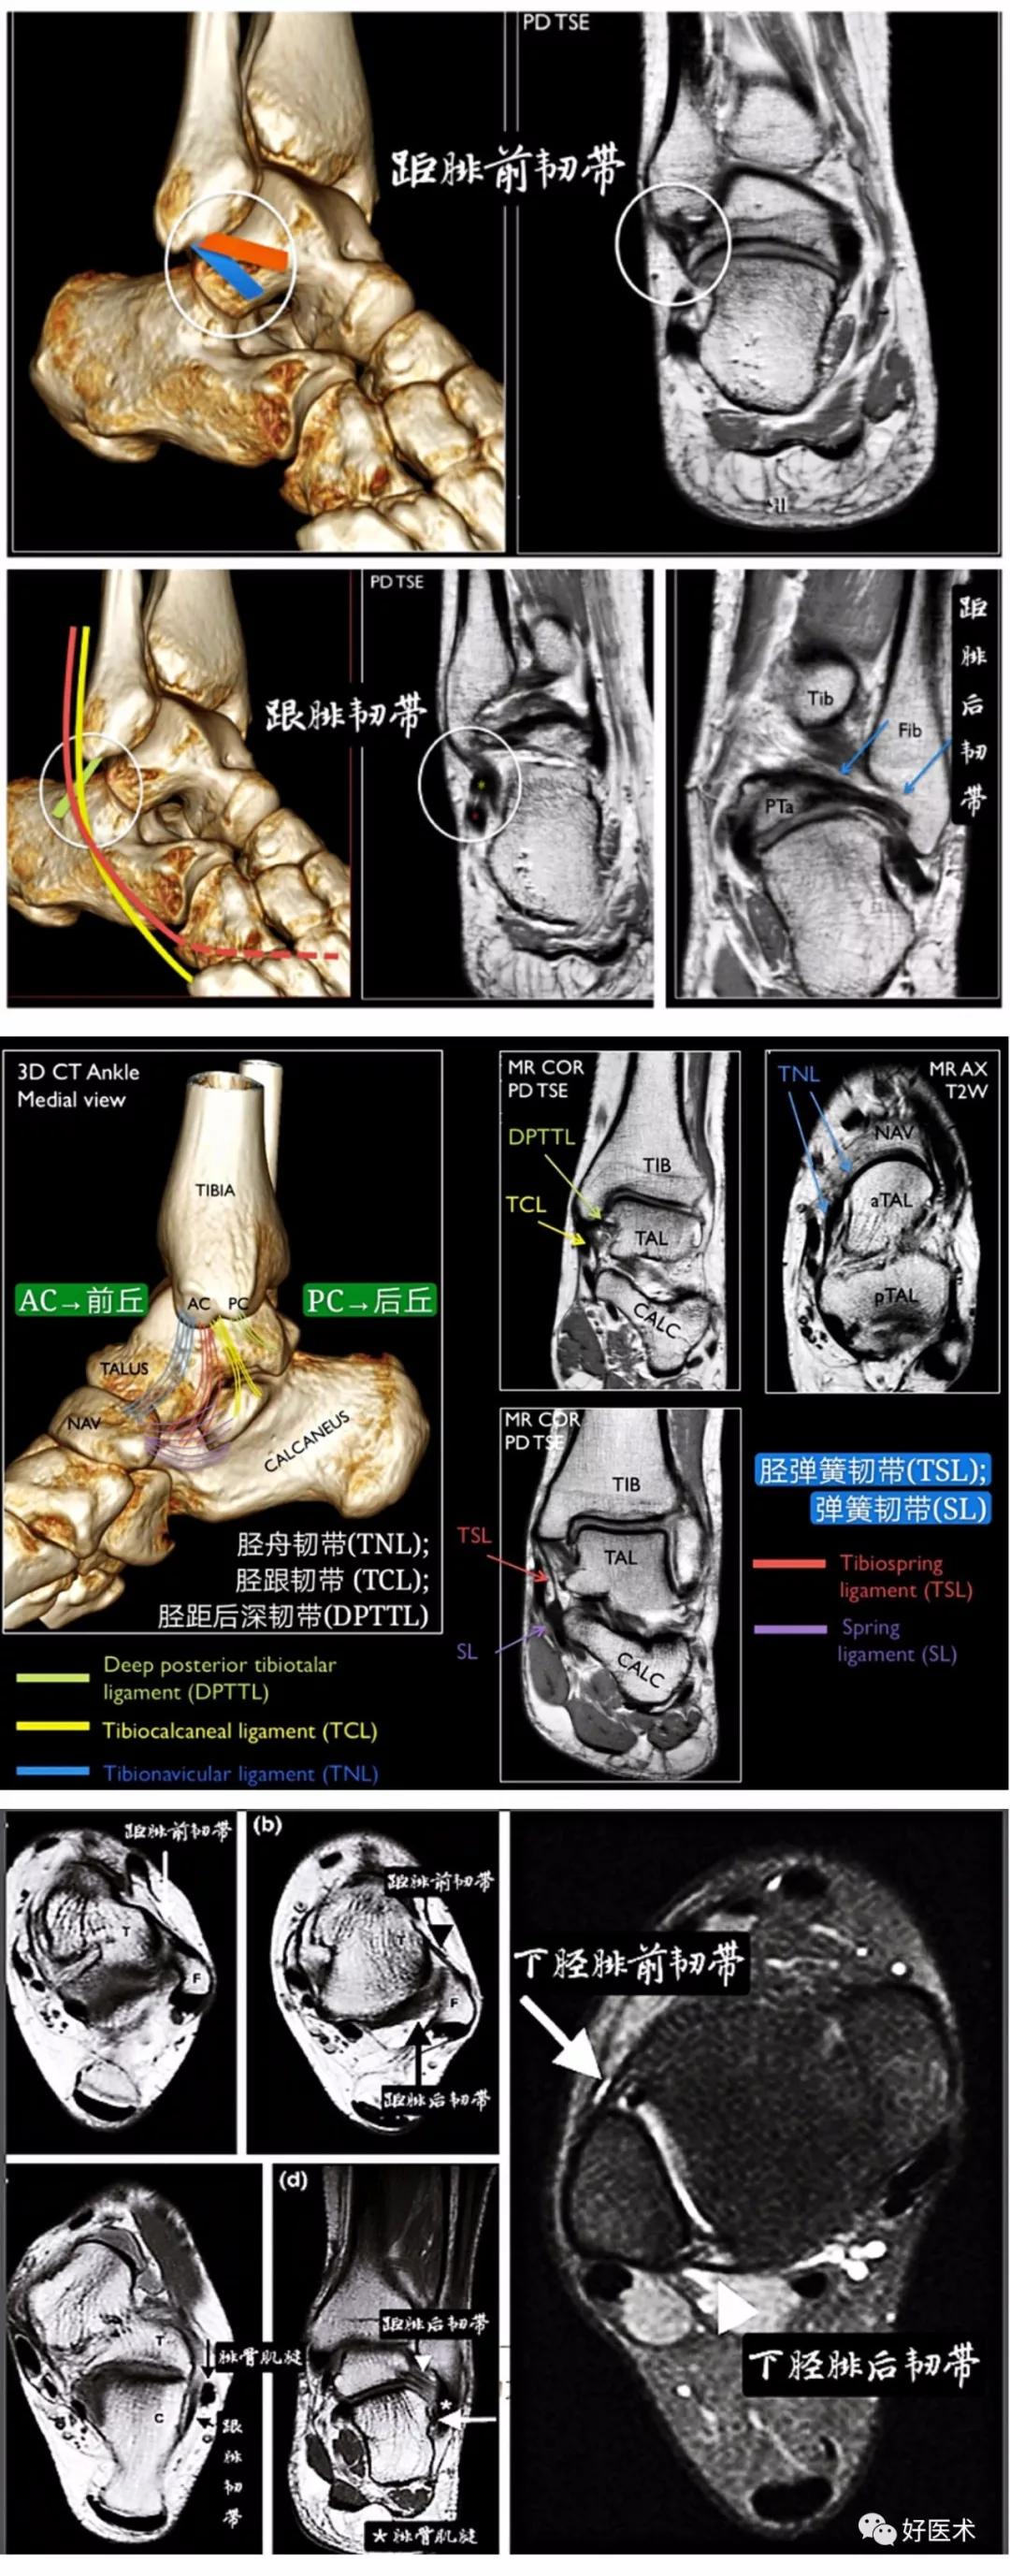

踝关节外侧副韧带由距腓前韧带、跟腓韧带和距腓后韧带组成。

距腓前韧带:起自外踝前缘,向前下斜行止于距骨颈外侧面,厚2~2.5mm。中立位时距腓前韧带与足的长轴平行,与小腿的长轴垂直。主要作用是限制距骨前移。

跟腓韧带 Calcaneofibular ligament : 起自外踝尖,向后下斜行止于跟骨外侧面,位于腓骨长短肌腱的深方。主要作用是限制跟骨内翻。

距腓后韧带 Posterior talofibular ligament: 起自外踝后部的外踝窝,水平向后止于距骨后外侧突,是3束中最强壮的1束。主要作用是限制距骨后移。

三角韧带,是多个韧带的复合体,韧带纤维起于内踝,走向呈像扇形方向展开于踝关节内侧面,分别附着于距骨、舟骨、跟骨。大多数学者认为三角韧带由深浅两层组成,两层间隔有脂肪垫,国外学者Milner and Soames提出浅层可分为4束,深层可分为2束。

浅层起于内踝前丘,横跨踝关节和距下关节,

☞包括胫舟韧带、胫弹簧韧带韧带、胫跟韧带和胫距后韧带浅层,呈扇形走行,止于舟骨背内侧面、载距突和距骨内侧结节;其中 胫弹簧韧带和胫舟韧带恒定存在 ,其余两束存在变异。

深层分为两束,仅横跨踝关节,

☞胫距前深韧带:起于前丘尖端和丘间沟,止于距骨内侧弧形关节面的前部。

☞胫距后深韧带:是整个三角韧带最为强大的部分,起于丘间沟和后丘的前面,止于距骨内侧弧形关节面的后部及距骨后内侧结节。其中 胫距后深韧带恒定存在 。

下胫腓韧带复合体

下胫腓韧带复合体包括下胫腓前韧带(AITFL)、下胫腓后韧带(PITFL)、骨间韧带(IOL)、下胫腓横韧带(TTL)以及骨间膜的远端部分。

下胫腓前韧带由胫骨下端的边缘向下外附着于外踝的前面及附近粗糙骨面上,主要限制腓骨外旋。

下胫腓后韧带则与下胫腓前韧带位置相当,纤维斜行,其下部纤维距胫骨下关节面尚有相当距离,因此使接受距骨的窝加深,恰好容纳距骨的后外侧部分,起到稳定距骨的作用,主要限制腓骨向后移动。

骨间韧带为短而坚实的纤维,实际上是骨间膜的向下延长部,纤维斜行,由内上方向外下方,起到加强胫腓骨的连结作用;

下胫腓横韧带横行于胫骨后面的下缘与外踝内侧面的三角间隙内,是加强的滑膜延长部,呈强韧索状,能防胫腓骨沿距骨上面向前脱位。

MRI拥有较高的清晰度和分辨率,可以多参数多方位扫描,从组织病理学方面反映病变,准确客观显示踝关节相关骨性和韧带损伤及程度。 MRI可以从3个解剖平面: 横轴面、矢状面及冠状面,显示踝关节韧带的解剖及其损伤程度。

矢状面能很好地显示距骨、胫骨后肌腱、跟距关节、跟腱、后及中距下关节、距舟关节、距胫关节,及这些关节软骨及关节腔,对显示跟腱的病变也有很大的帮助;

冠状面能清楚地显示出腓距关节、距胫关节、距跟关节以及外踝的结构,特别是胫骨、腓骨与距骨之间的关节面,同时可显示它们之间的韧带腓骨与距骨之间的关节面,同时可显示 胫距后韧带和距腓后韧带 及胫骨后肌腱;

横轴位能很好地显示出 胫腓前韧带、距腓前韧带 。